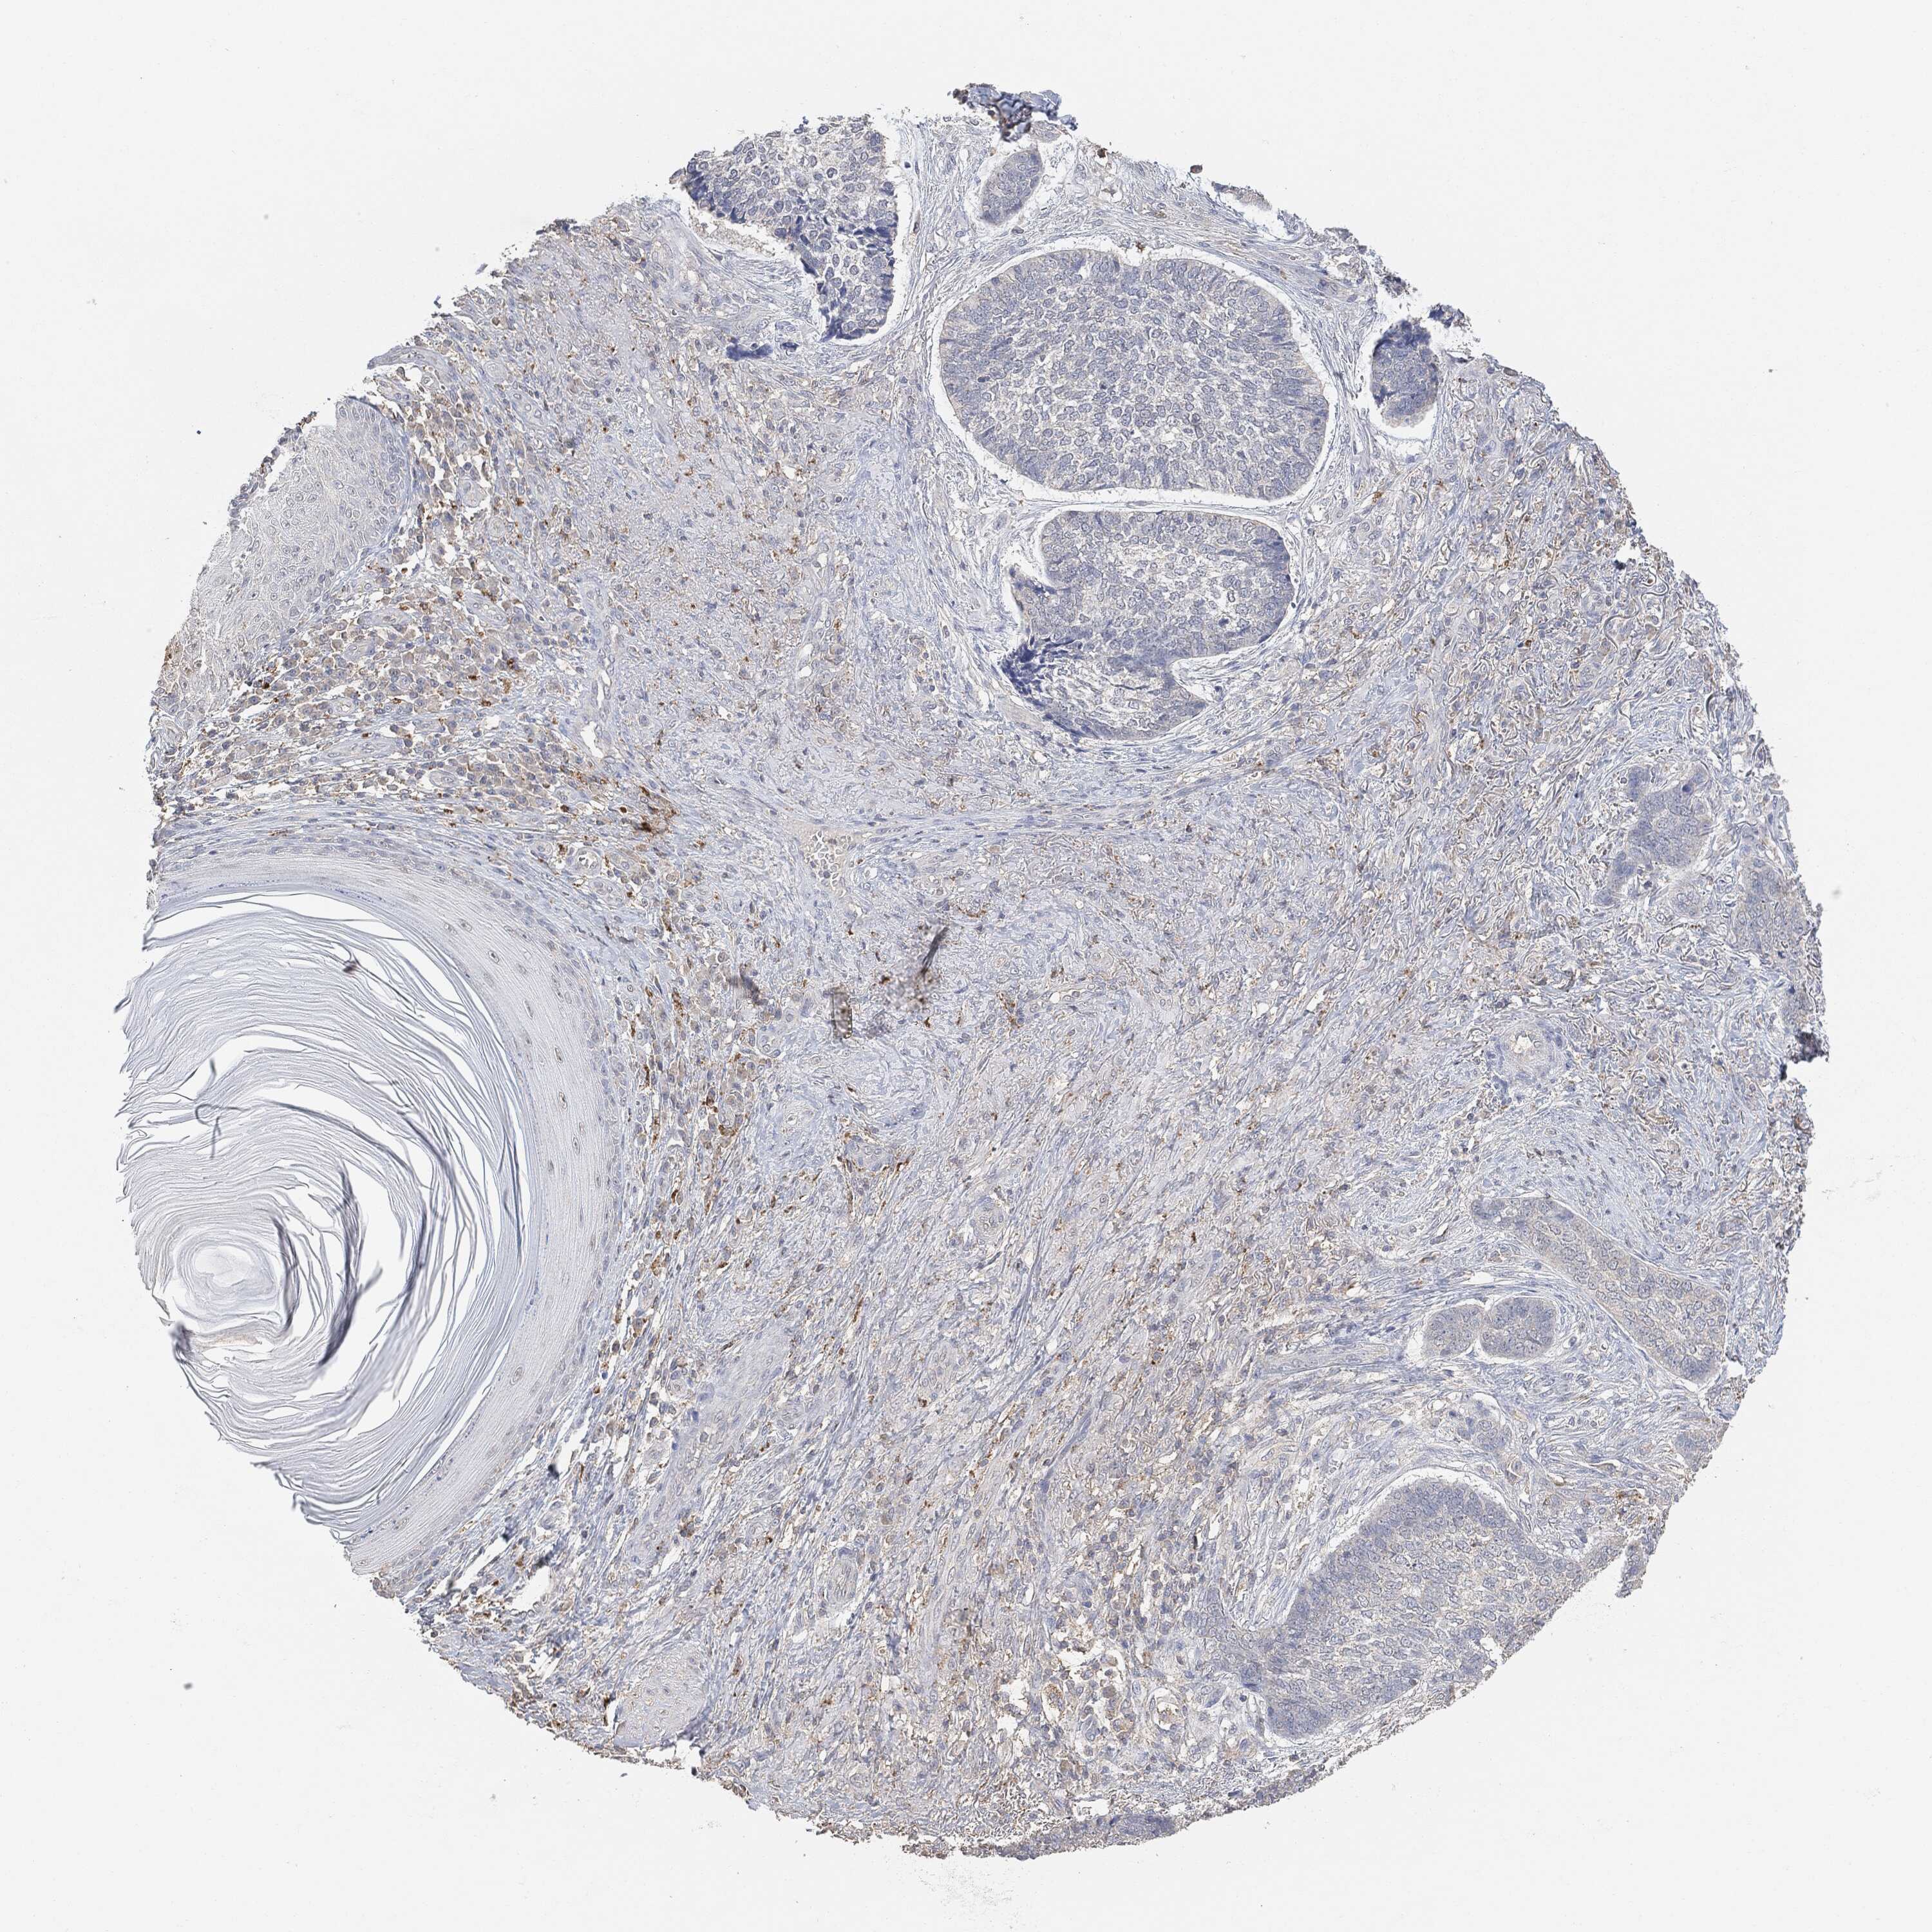

SKIN CANCER - Protein expressioni

A mouse-over function shows sample information and annotation data. Click on an image to view it in a full screen mode. Samples can be filtered based on level of antibody staining by selecting one or several of the following categories: high, medium, low and not detected. The assay and annotation is described here.

Antibody stainingi

Antibody staining in the annotated cell types in the current human tissue is reported as not detected, low, medium, or high, based on conventional immunohistochemistry profiling in selected tissues. This score is based on the combination of the staining intensity and fraction of stained cells.

Each image is clickable and will lead to virtual microscopy that enables deeper exploration of all samples and also displays staining intensity scores, fraction scores and subcellular localization as well as patient and tissue information for each sample.

Squamous cell carcinoma in situ, NOS